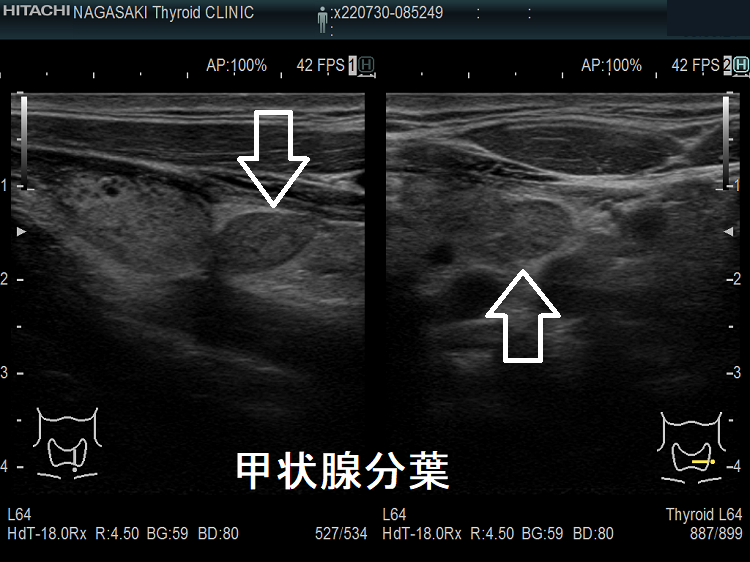

頚部異所性甲状腺でなく甲状腺分葉

頚部異所性甲状腺のように見えても、微妙に甲状腺本体と連続していて甲状腺分葉の場合があります。

頚部異所性甲状腺でなく甲状腺分葉(拡大)

頚部異所性甲状腺でなく甲状腺分葉 超音波(エコー)画像 矢状断 (拡大)